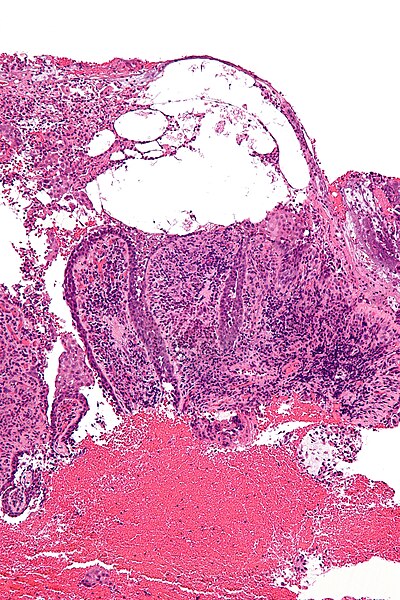

Контуры патологии — Пемфигус

Неопухоль кожи

Паттерны пузырно-пузырчатой и акантолитической реакции

Пемфигус